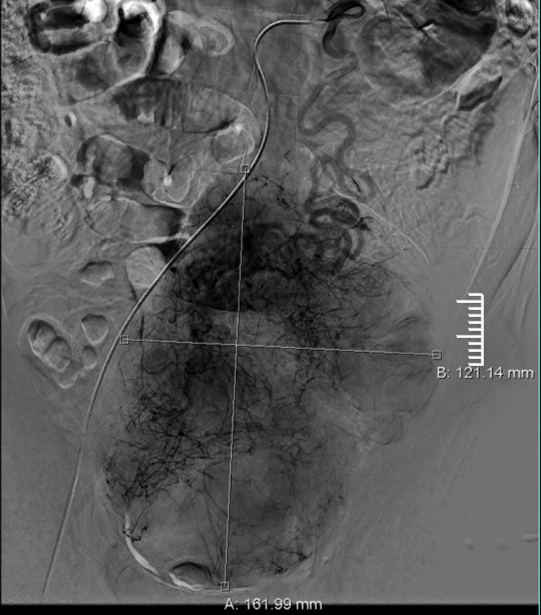

术前影像图。院方供图

入院后,通过盆腔核磁共振检查,发现患者双侧隐睾、异味睾丸恶性病变。因患者左中下腹腔巨大占位,邻近组织不同程度受压移位,左侧精囊腺增大并与上述肿块分界不清,肿瘤血供极其丰富,盆腔占位性病变与周围组织粘连,不能排除侵犯髂血管可能,手术出血风险较高,难度系数大。

重医附二院泌尿外科刘川教授及其团队经反复讨论,精心准备,联系血管外科、麻醉科等多科会诊,讨论手术方案,在泌尿系肿瘤MDT团队会诊建议下由刘曦教授行术前肿瘤主要动脉超选择性插管化疗栓塞术,降低术中出血风险及肿瘤复发率;针对术中可能发生的各种风险制定了详细的应急预案。